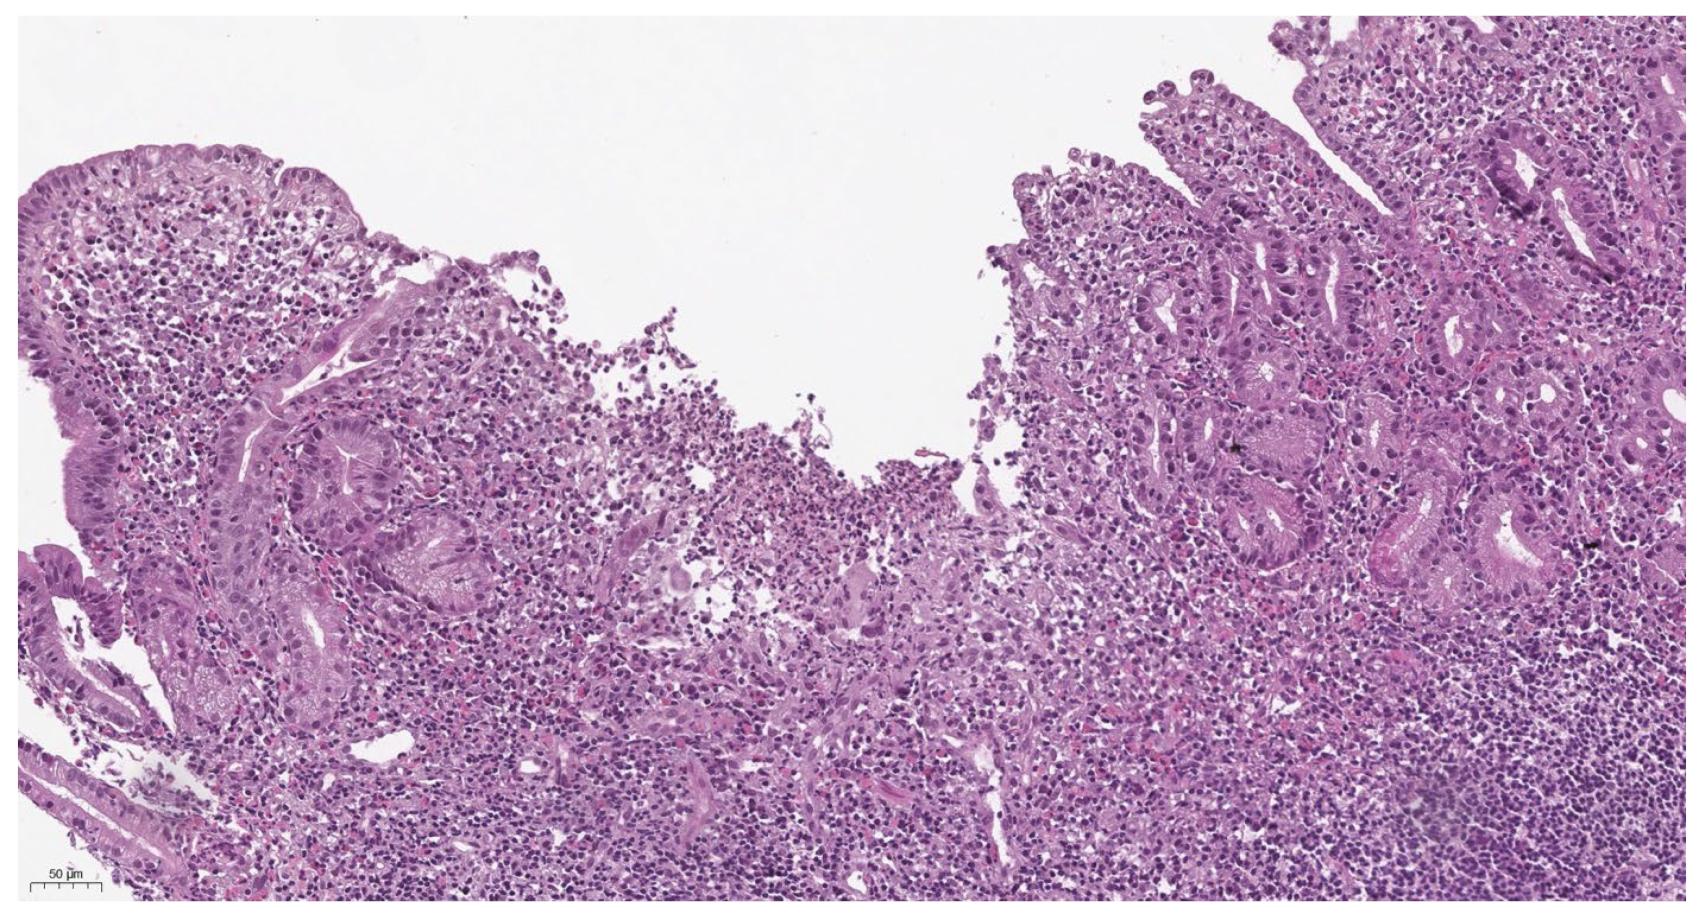

3.5. Morphological Characteristics

- Conrad, M.A.; Carreon, C.K.; Dawany, N.; Russo, P.; Kelsen, J.R. Distinct Histopathological Features at Diagnosis of Very Early Onset Inflammatory Bowel Disease. J. Crohn’s Colitis 2019, 13, 615–625. [Google Scholar] [CrossRef] [PubMed]